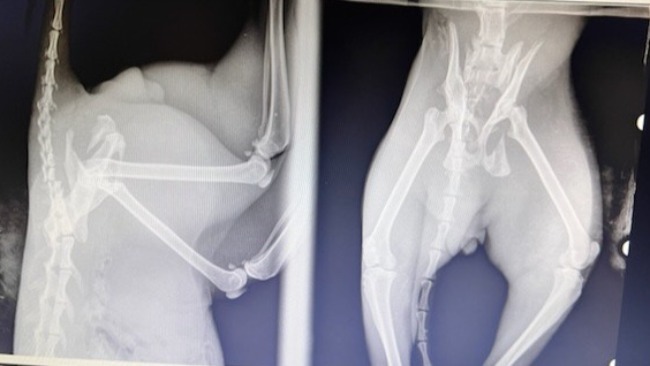

Po poukładaniu sobie w głowie słów lekarza i przekładając określenia medyczne na możliwe do zrozumienia - złamanie miednicy (i to po raz kolejny, bo ze zdjęcia RTG wyszło, że już wcześniej przeszedł takie, które uległo samozaleczeniu), złamanie kości krzyżowej, prawdopodobnie ogon do usuniecia (do późniejszej oceny), być może po otwarciu okazać się także, że staw biodrowy też uszkodzony i główka kości udowej do usunięcia, ewentualne zwężenie miednicy, dodatkowo sprawy neurologiczne, kwestia czy kocurek będzie potrafił się wypróżniać, dawał się obsługiwać i czy nie będzie agresywny...

Badanie wykonano i niestety ukazała się rzeczywista mnogość urazów, pięciu złamań w obrębie miednicy i kości krzyżowej, niewiadomy stan neurologiczny, dodatkowo nieoddawanie moczu, bardzo niepomyślne rokowania...